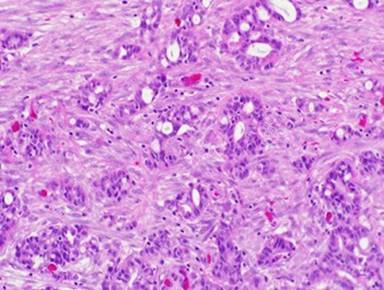

Twenty-one months following pancreaticoduodenectomy, he was evaluated in clinic for a symptomatic right-sided groin mass and a CT scan showed free fluid in the right inguinal canal (Figure 2). He was subsequently taken to the OR and underwent outpatient right-sided hydrocele repair and excision of a non-communicating loculated cyst of the spermatic cord. Postoperatively, he recovered uneventfully. Surprisingly, despite no gross evidence of metastatic disease in the sac, pathology revealed metastatic moderately differentiated adenocarcinoma consistent with a pancreaticobiliary primary (Figure 3, 4, 5).

Figure 4. High power view of tumor in the hydrocele sac. The tumor forms many simple glandular structures (hematoxylin and eosin stained sections, 200X original magnification). |